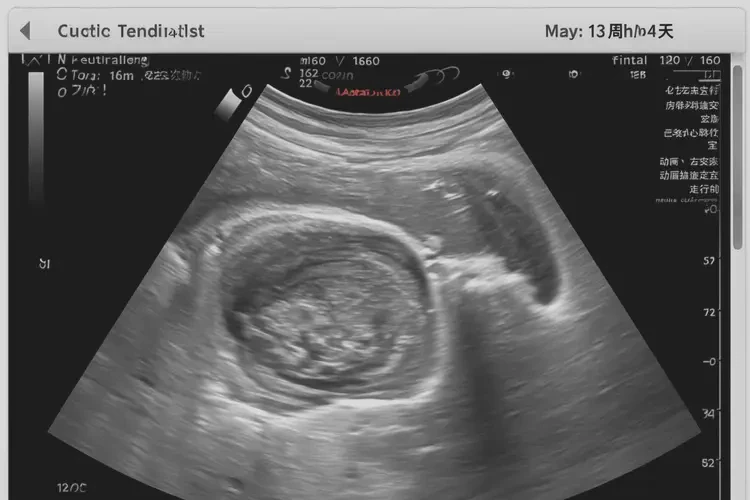

162次/分钟

孕13周4天的胎心为162次/分钟,通常在正常范围内。胎儿心率在孕早期较快,随着孕周增加会逐渐减慢。以下是关于胎心的详细信息:

- B超检查:可同时观察胎儿心率和心脏结构,提供更全面的评估。

孕13周4天的胎心为162次/分钟,通常在正常范围内。如果出现胎心异常情况,应及时就医,以便医生进行进一步评估和处理。定期进行产检和胎心监测,有助于及时发现和处理潜在问题,确保胎儿健康发育。